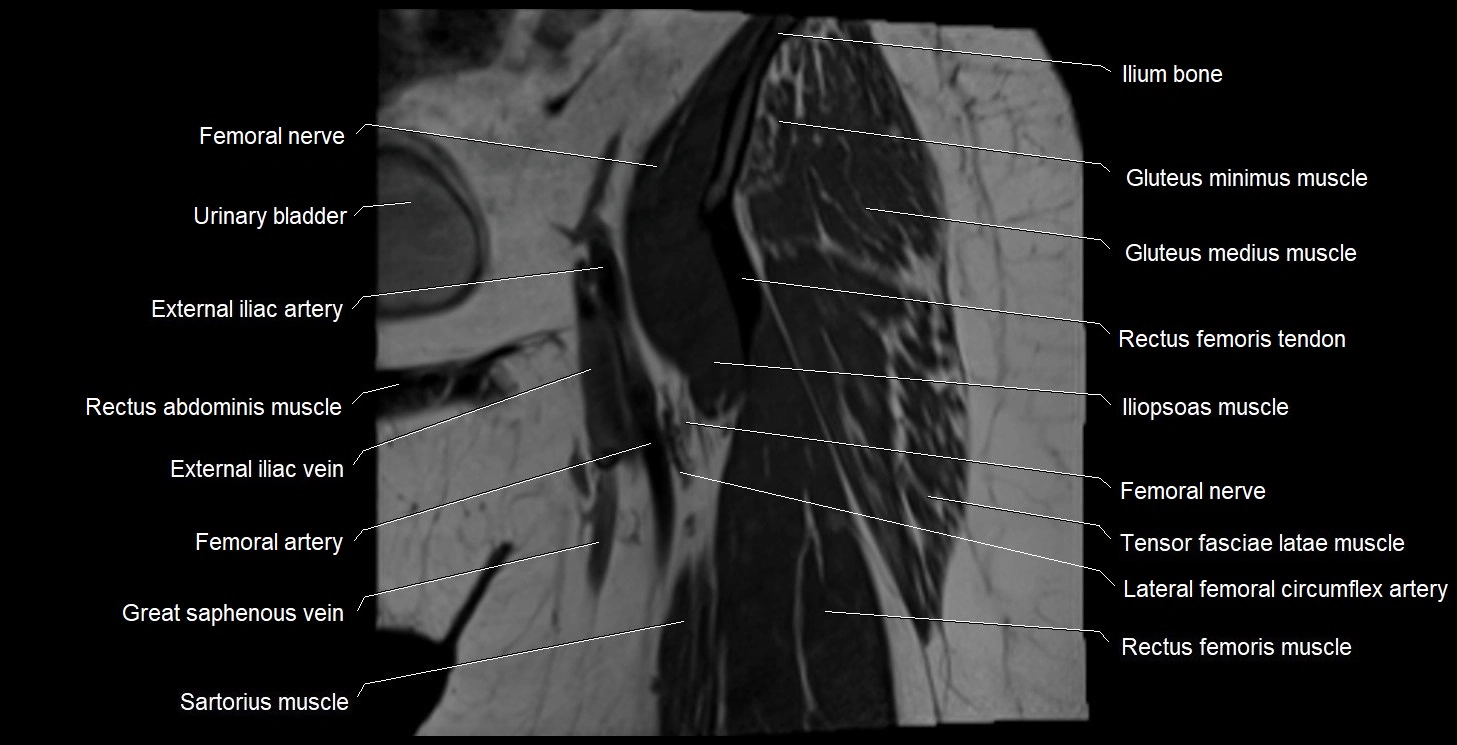

- Femoral nerve

- Iliopsoas muscle

- Rectus femoris muscle

- Rectus femoris tendon (Proximal tendon of rectus femoris)

- Sartorius muscle

- Tensor fasciae latae muscle

- Urinary bladder